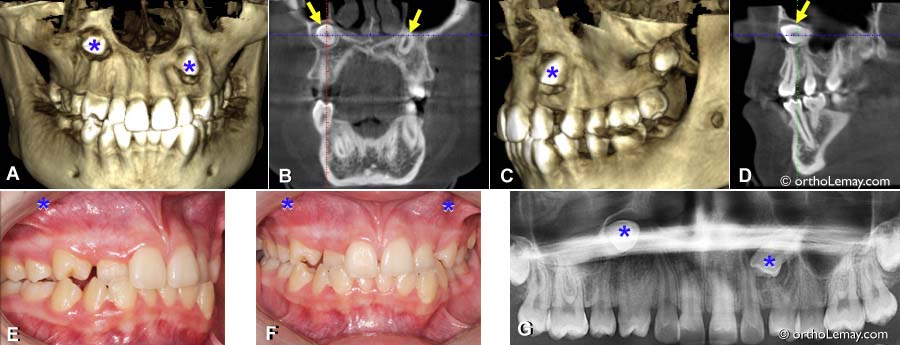

(A à D) Tomodensitométrie volumique à faisceau conique (TVFC) montrant les canines supérieures à l’horizontal et presque dans le plancher du nez (* bleus).

(E, F) Vue clinique où la position approximative des couronnes des canines incluses est indiquée.

(G) Radiographie panoramique. Bien qu’on puisse deviner la malposition extrême des canines, une telle radiographie ne donne pas autant d’information qu’un scan en 3D (TVFC).

À cause de la position très haute et horizontale des canines ainsi que du manque d’espace important à l’arcade supérieure, il fut décidé d’extraire ces 2 dents incluses.